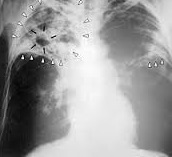

Lancée en partenariat avec les départements gouvernementaux concernés et la société civile et avec l'appui du Fonds mondial de lutte contre le sida, la tuberculose et le paludisme, cette campagne ambitionne de renforcer le dépistage de la tuberculose chez les groupes de populations à haut risque, au niveau des provinces et des préfectures les plus touchées de six régions, à savoir Fès-Boulemane, le Grand Casablanca, Rabat-Salé-Zemmour-Zaer,

Gharb-Chrarda-Béni Hssen, Tanger-Tétouan et Souss-Massa-Draâ.

Il est à rappeler qu’un plan national d'accélération de la réduction de l'incidence de la tuberculose 2013-2016 a été mis en place en vue d'augmenter le taux de détection des cas de tuberculose de 85% actuellement à plus de 95% d'ici 2016, soit plus de 4.800 cas chaque année, à raison de 400 cas/mois sur toutes les provinces et régions.

Sur le plan international, l'Organisation mondiale de la santé recense plus de 9 millions de personnes ayant contracté la tuberculose en 2013, dont 1,5 million en sont mortes.

Sur le plan national, le ministère de la Santé a enregistré 27.745 nouveaux cas de tuberculose en 2014. Tous les cas bénéficient d'une prise en charge thérapeutique gratuite dans les établissements de santé, de 6 mois minimum, dont certains nécessitent des traitements de plus de 18 mois, d'un coût de 34,000 dirhams par malade atteint de tuberculose multi-résistante.

Le Programme national de lutte antituberculeuse (PNLAT) conduit par le ministère de la Santé, a permis un recul de l'incidence depuis 1996. Le taux de détection des cas est maintenu, à ce jour, à plus de 85% et le taux de succès thérapeutique atteint 90%.

Ces résultats ont été possibles grâce aux efforts combinés du ministère et de ses partenaires, notamment le Fonds mondial de lutte contre le Sida, le paludisme et la tuberculose, ainsi que les associations de le société civile qui réalisent un travail de proximité en matière de sensibilisation des malades tuberculeux et de relance des personnes malades ayant abandonné leurs traitements.

Malgré ces tendances positives, la lutte contre la tuberculose reste en deçà des aspirations, tant les déterminants de la maladie sont multiples et se rapportent essentiellement aux conditions socioéconomiques défavorables.

L'infrastructure spécialement dédiée à la lutte antituberculeuse est constituée de 62 centres de diagnostic et de traitement de la tuberculose et des maladies respiratoires (CDTMR) répartis sur l'ensemble des provinces, 72 centres de santé intégrés et 2 services de traitement spécialisé de la tuberculose multi résistante au niveau des CHU de Rabat et de Casablanca.